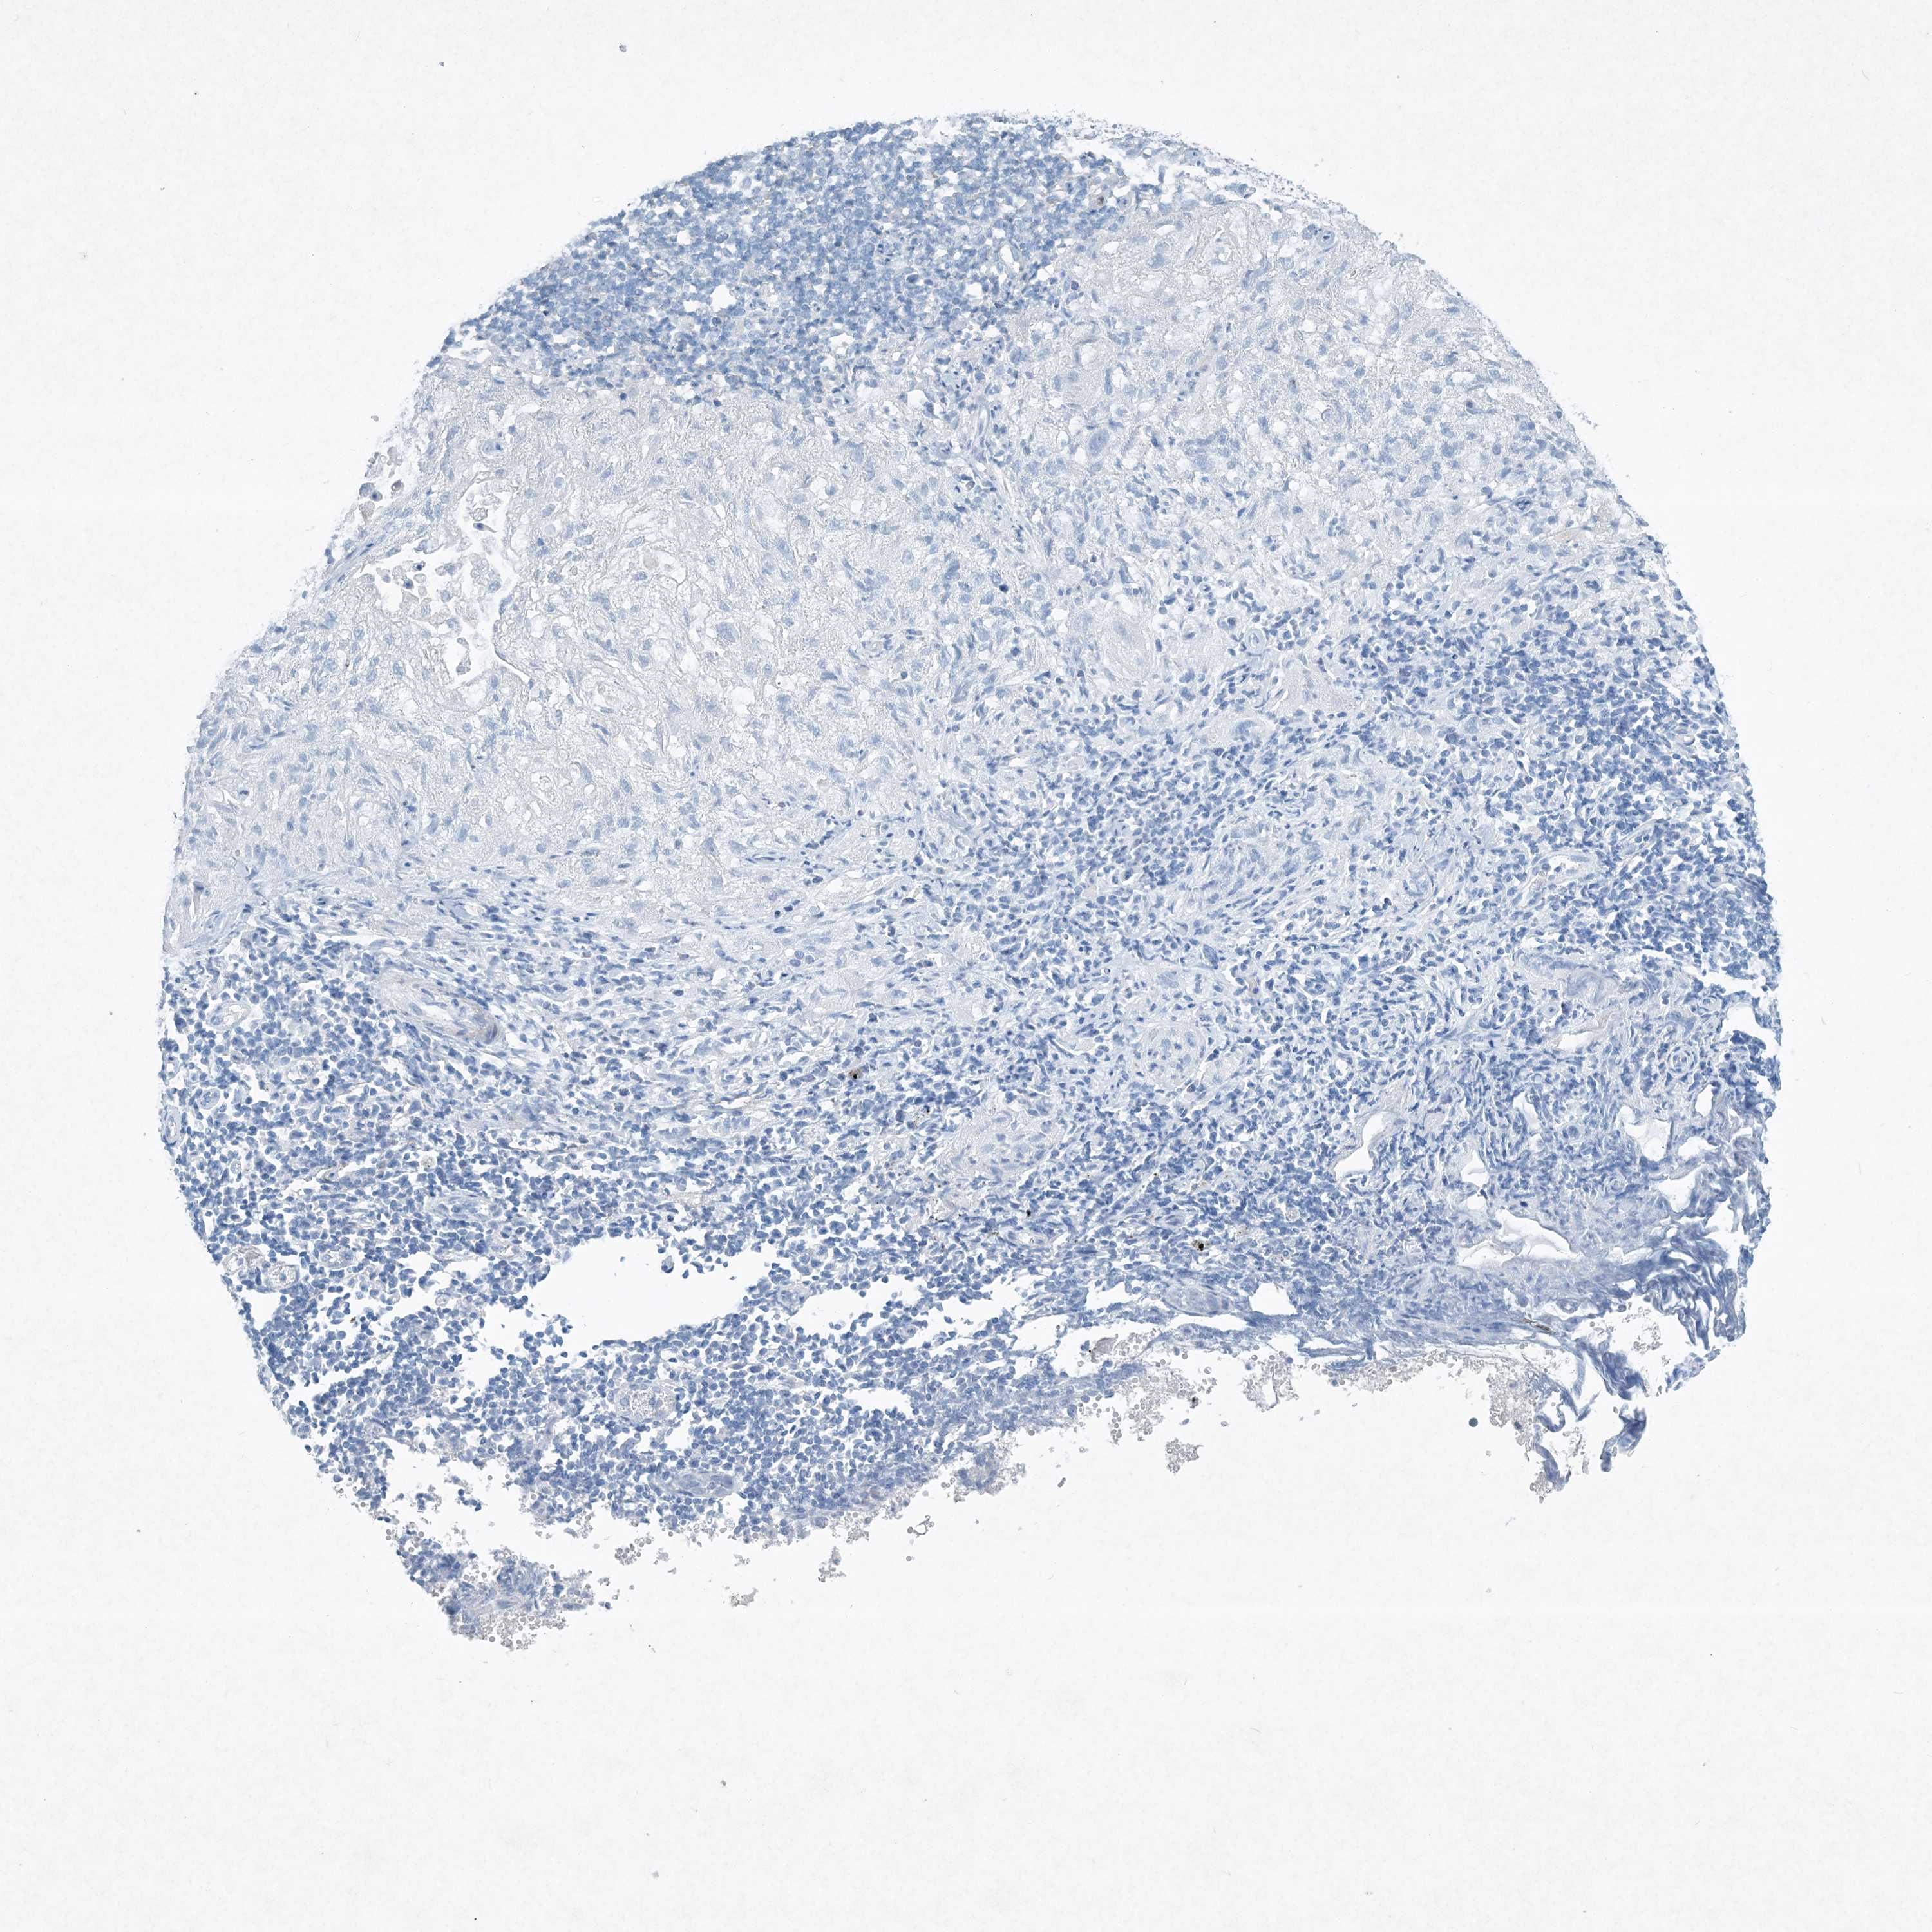

CANCER LUNG CANCER Show tissue menu